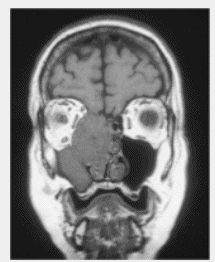

with inoperable tumors. Contrast-enhanced CT or MRI

scans before initiation of treatment are crucial to

demarcate extension of the tumor. Treatment planning with CT

for determination of tumor extension is extremely important.

Because of the proximity of esthesioneuroblastoma to the

optic nerves, optic chasm, and the brainstem, the precision

of treatment setup, target volume definition, and dose

homogeneity dictate tumor control and the sequelae of